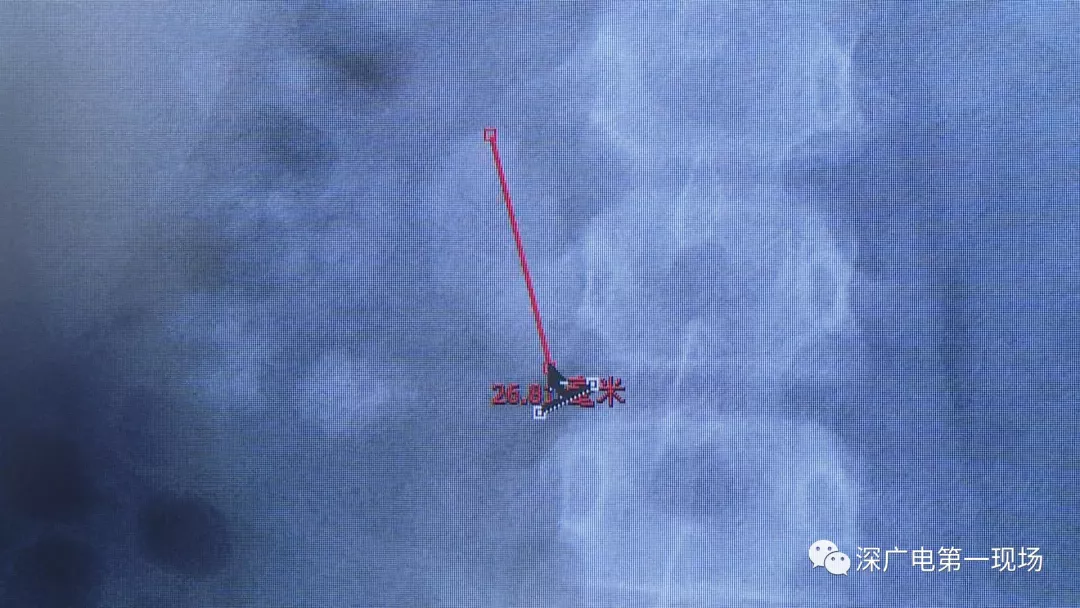

小轩这种情况,其中,最大的结石长约2.7厘米,宽约1.7厘米,体积堪比鹌鹑蛋,不但造成了尿路堵塞,还导致了右肾中度积水。